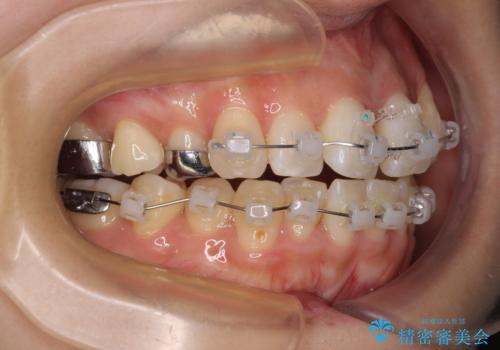

- クリアブラケット

- 1年3ヶ月

上顎の急速拡大装置を使用して上顎骨を側方に拡大することで上顎歯列を拡大し、下顎歯列も拡大できるようにすることで、歯列を整えることとしました。